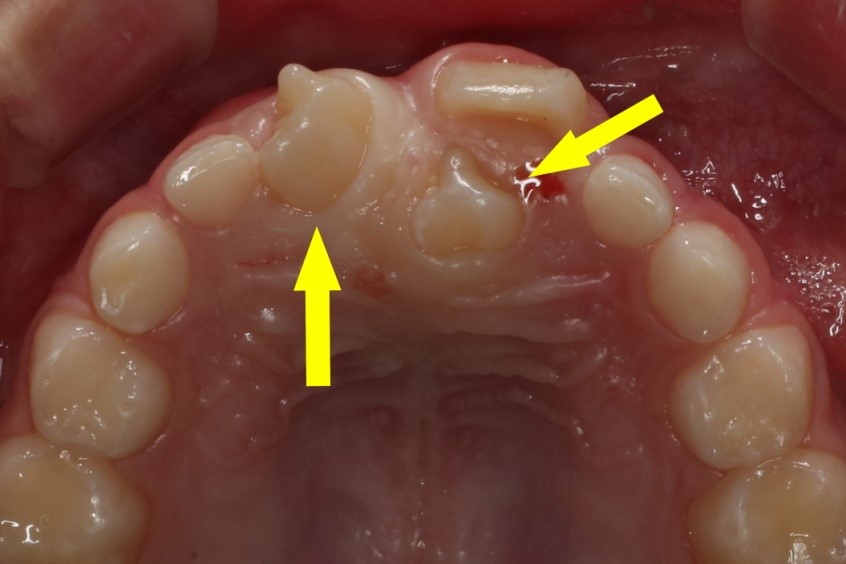

과잉치는 유치보다는 영구치에서 주로 발생하며, 위턱 대문니 주변에 잘 나타난다.  2개의 과잉치가 위치해있다.

과잉치의 정확한 원인은 밝혀지지 않았으나, 발육하는 과정 중 치아가 만들어지는 상피조직의 과잉활성 때문으로 추측된다. 유전적인 영향도 있어 부모·형제가 과잉치를 가지고 있으면, 자녀에게도 발생할 확률이 높다. 유치보다는 영구치에서 잘 발생하며 대개 위턱 대문니 근처에서 원추 형태로 나타난다.